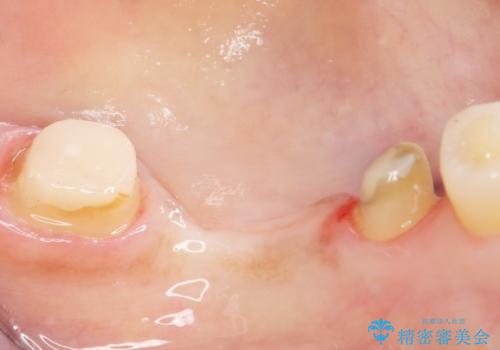

- 奥歯の痛みを主訴に来院された患者様です。

精査したところ、ブリッジの支台歯となっている左下の奥歯(左下7)は大きなう蝕により神経が死んでいました。

根管治療後、メタルボンドブリッジによる補綴治療を行いました。